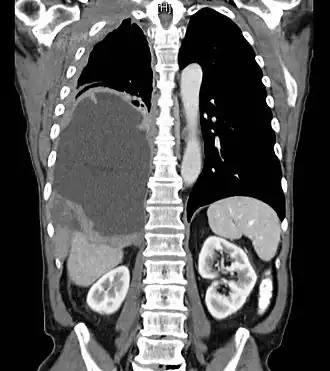

Tomodensitométrie thoracique montrant un mésothéliome dans le poumon droit (à gauche dans l'image).

Même si le mésothéliome peut être dépisté par une simple radiographie du thorax, l'examen de référence est le scanner thoracique[8], l'IRM pouvant constituer une alternative[9]. La tomographie par émission de positons permet de faire le bilan d'extension[10].